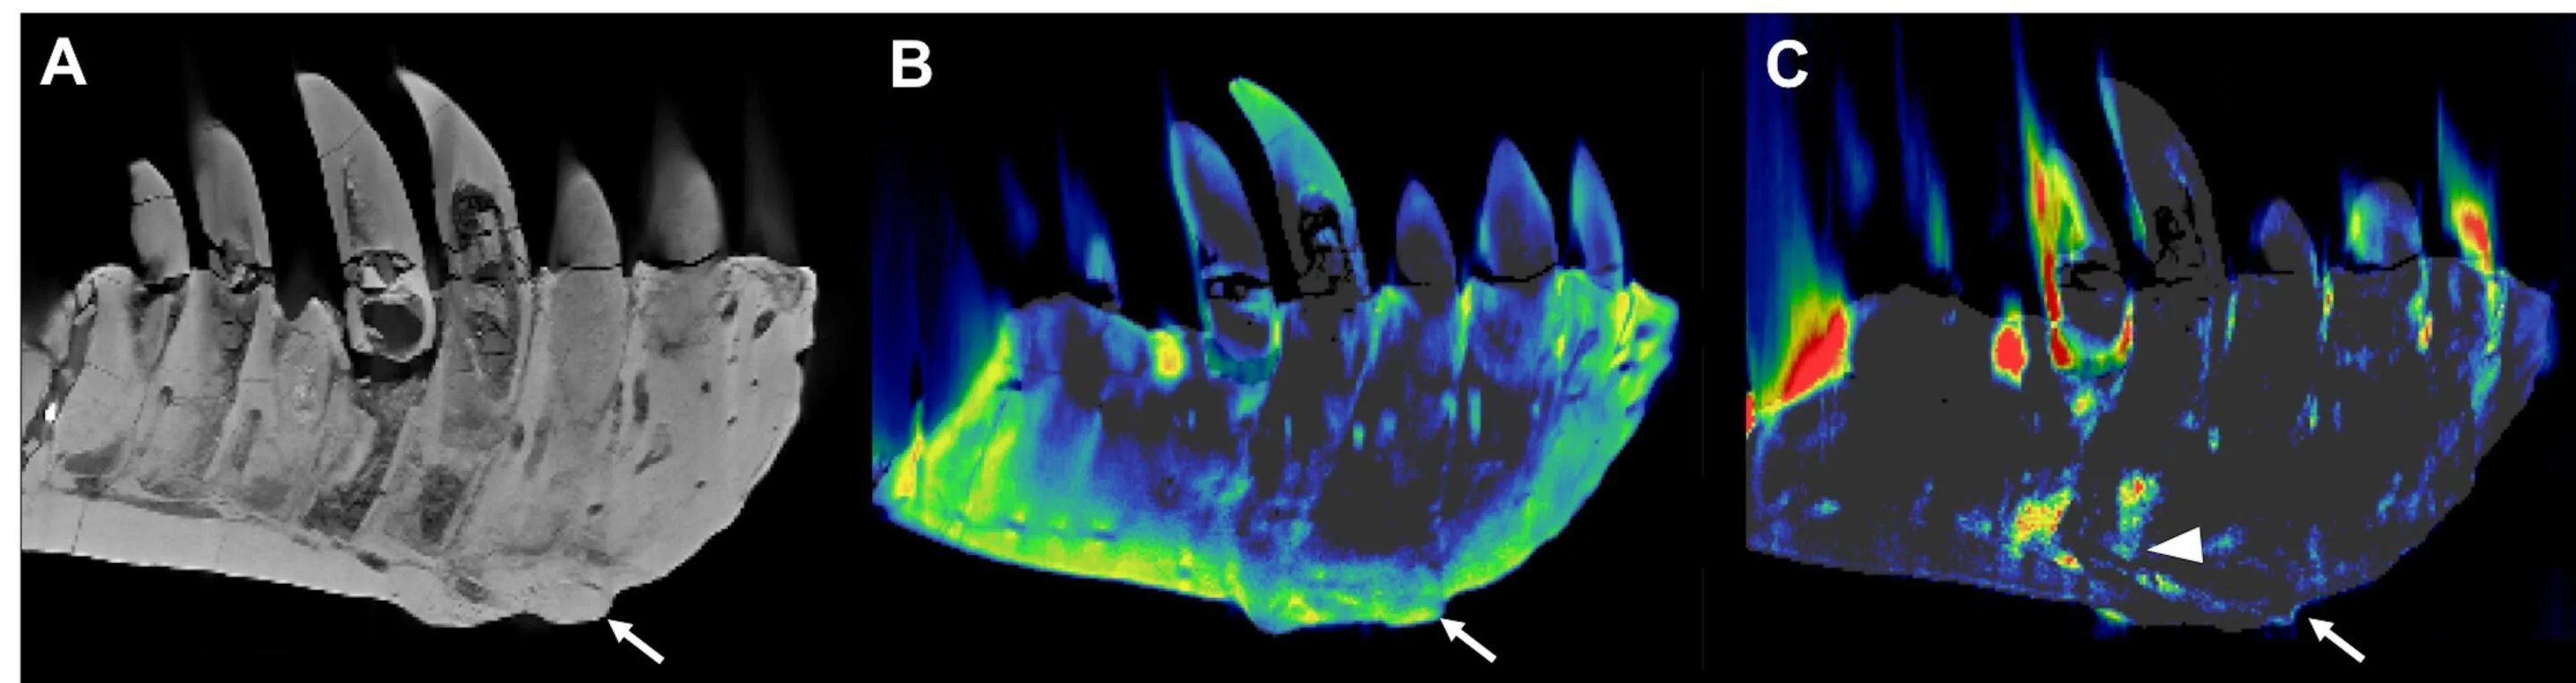

Досліджуваний череп тиранозавра / Фото Phys

Науковці використали клінічний томограф, який робив зображення завдяки так званій двоенергетичній комп'ютерній томографії (dual-energy computed tomography, DECT). Завдяки цьому вдалося просканувати та отримати зображення лівої нижньої щелепи прадавнього хижака.

Науковці побачили там потовщення, яке доходило до коріння одного із зубів. У цьому ж потовщенні була виявлена висока концентрація фтору, що свідчило про знищену щільність кісткової тканини. Вчені зробили висновок, що тиранозавр хворів на остеомієліт – інфекційне запалення кісток.